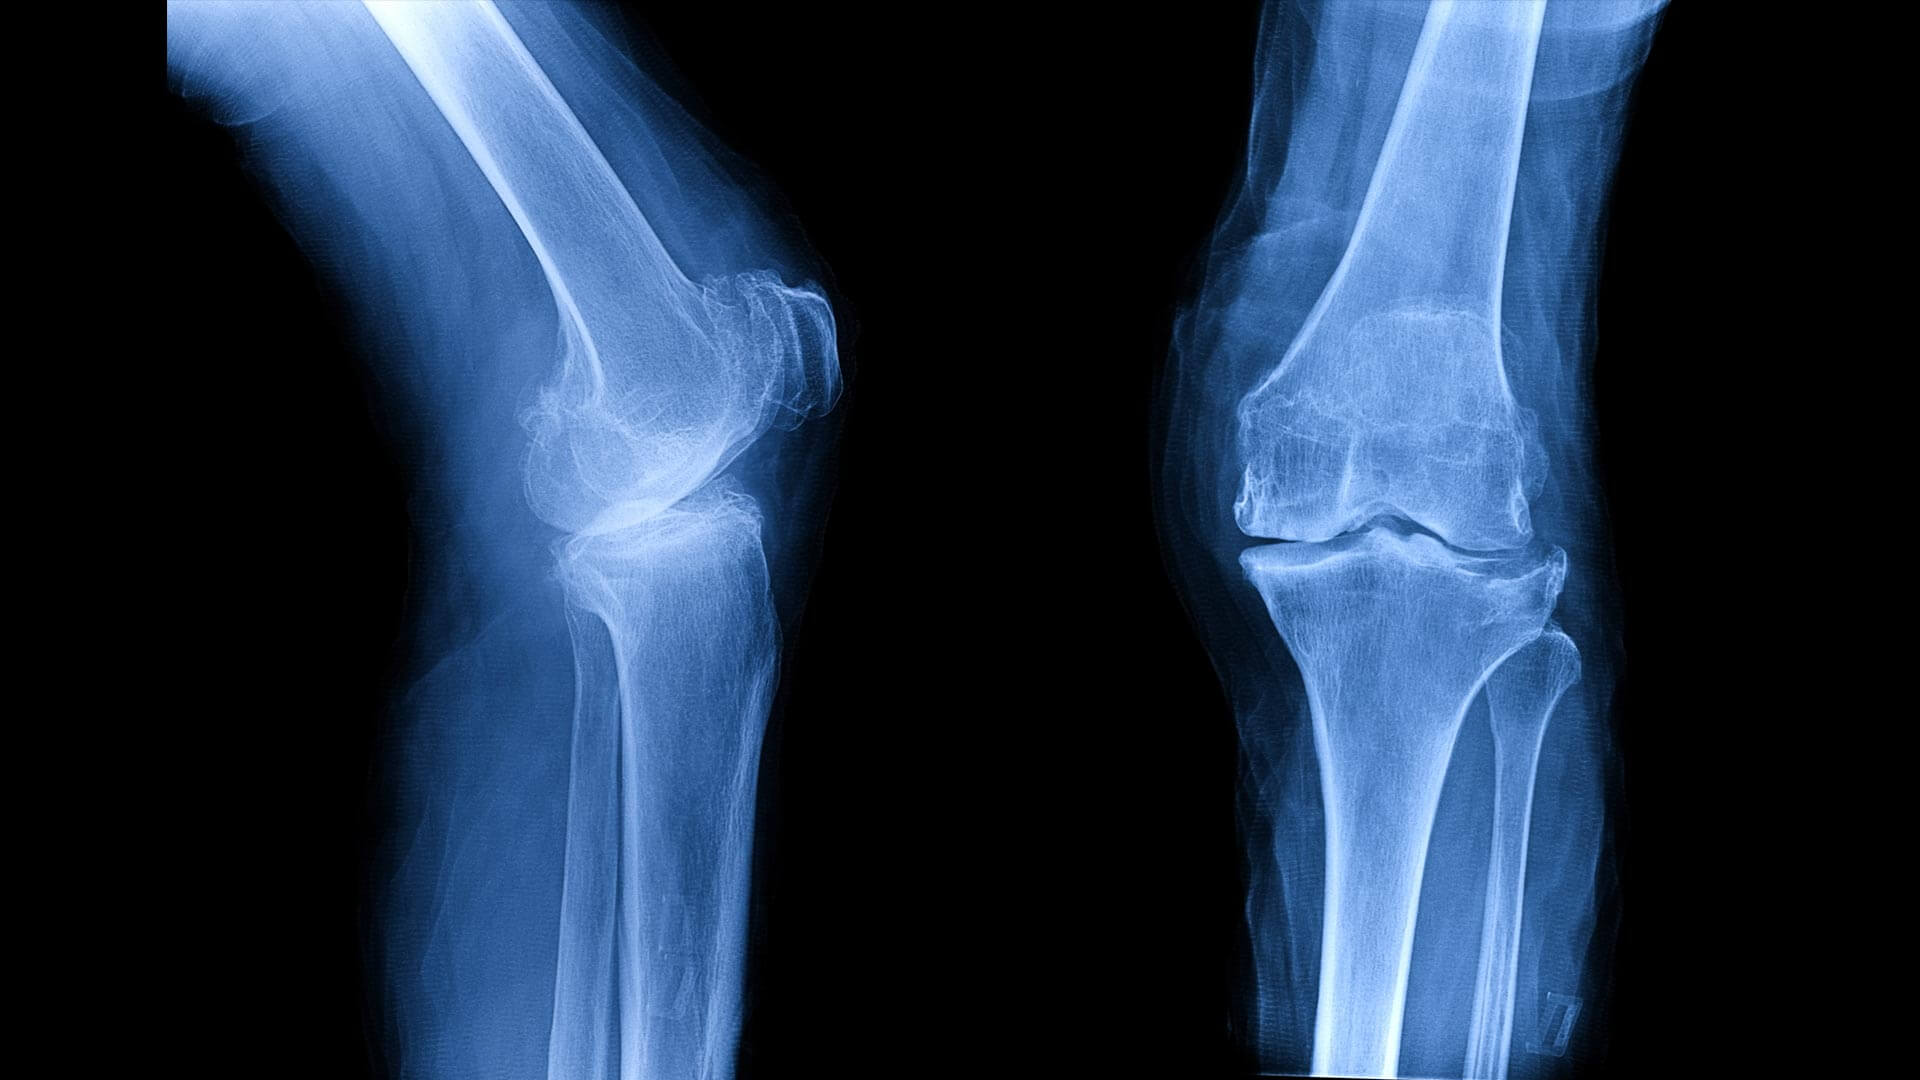

如果膝关节出现畸形, 无论是内翻,还是外翻, 下肢的生物力学都会有显著的改变。

而这种改变就会引发很多问题,比如 膝骨关节炎。

甚至到最后很多医生已经分不清是膝骨关节炎导致的膝关节畸形,还是由于膝关节畸形导致的膝骨关节炎。

具体说来我们所谓的 X形腿以及O型腿, 其实都是膝关节畸形的表现。

如果可以用外侧楔形鞋垫或者内侧楔形鞋垫,因地制宜就可以帮助足底改变压力力线,进而避免一些膝关节的损伤。

不过具体该选择哪种鞋垫应该怎么使用,还是应该咨询医生,不要太武断。